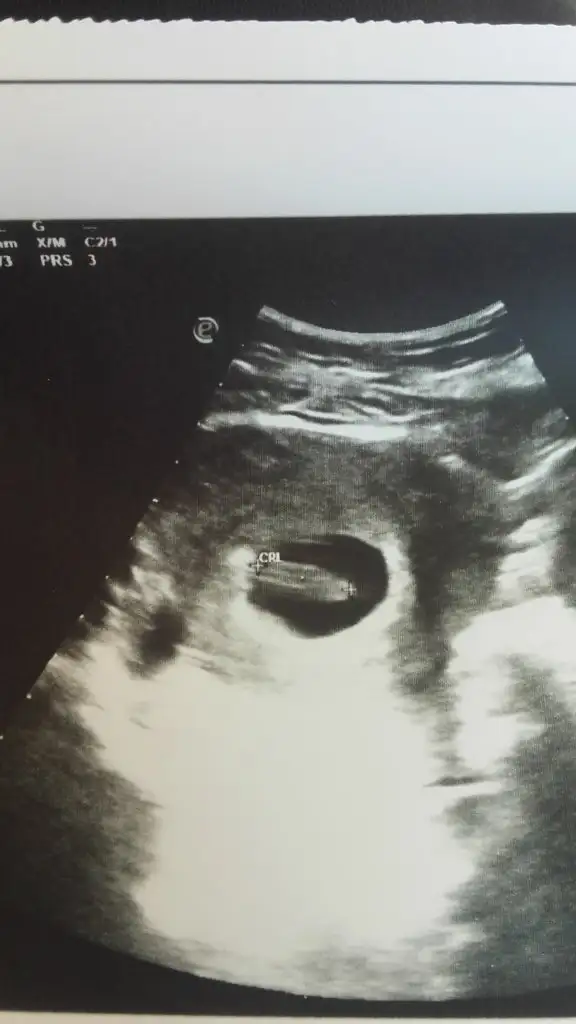

Keseye bakılırsa kız.

Pozisyona bakılırsa, erkek.

Ben erkek diyorum kesenin istisna oluşundan ötürü.

Benimde 12 haftalik merak ettim tahmininiz nedir?